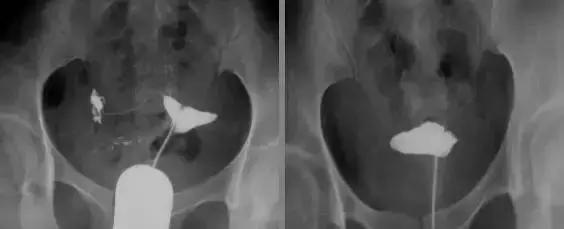

慢性输卵管炎

输卵管伞周粘连